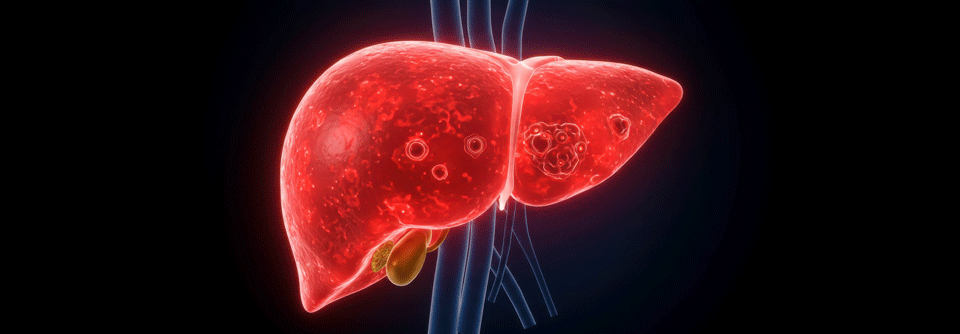

Leberzellkarzinom: Entwicklungen bei Frühdiagnostik und Therapie

War die Diagnose eines Leberzellkarzinoms lange Zeit fast gleichbedeutend mit einem zeitnahen Tod, so hat sich in den vergangenen zehn Jahren eine Menge in Sachen Frühdiagnostik und Therapie getan. An einigen wichtigen Stellen hapert es aber noch.

Einen bösartigen Lebertumor möglichst früh zu erkennen, damit ihn Chirurgen schnell resezieren können, stellt bis dato eine große Herausforderung dar. Trotz aller Fortschritte der vergangenen Jahre ist die Detektion hepatozellulärer Karzinome gerade in dieser wichtigen Phase noch lange nicht optimal, schreiben der Hepatologe Dr. Ju­ Dong­ Yang,­ Cedars-Sinai Medical Center, Los Angeles, und seine Kollegin Dr. Julie­ Heimbach­ vom Mayo Clinic College of Medicine in Rochester. Doch es geht voran und Ärzte können bereits jetzt einiges für Patienten tun.